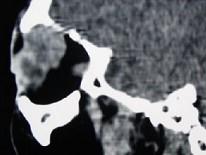

问题 女,36岁,左眼眶外上部可触及一无痛性包块有2年,眼球向内下方突出,CT检查如图,最可能诊断为()

选项 A.泪腺良性混合瘤 B.泪腺恶性上皮性肿瘤 C.炎性假瘤 D.淋巴瘤 E.淋巴瘤样增生

答案 A